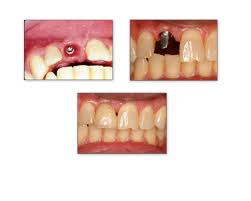

Τα εμφυτεύματα τοποθετούνται με τοπική αναισθησία, και με τη βοήθεια ειδικών ακτινογραφιών και μηχανημάτων εξασφαλίζεται ότι θα μπουν στη σωστή θέση. Μετά την επέμβαση, τα εμφυτεύματα συνήθως καλύπτονται από τα ούλα και παραμένουν στη γνάθο 2-6 μήνες για να ενσωματωθούν με το οστό. Στο διάστημα αυτό, οι ασθενείς χρησιμοποιούν προσωρινές γέφυρες ή οδοντοστοιχίες, για να μπορούν να μασούν και να μιλούν χωρίς πρόβλημα. Κατόπιν, αρχίζει η κατασκευή και η τοποθέτηση του πορσελάνινου δοντιού πάνω στο εμφύτευμα.

• Σε ορισμένες περιπτώσεις, όπως π.χ. όταν η οστική πυκνότητα το επιτρέπει, δεν αποκλείεται να γίνει η προσθετική εργασία μαζί με την τοποθέτηση του εμφυτεύματος, με ελαχιστοποίηση του χρόνου αναμονής. Ωστόσο, συμβαίνει συχνά κατά τη διαδικασία να μην υπάρχει στην περιοχή το απαραίτητο οστό, οπότε χρειάζεται να χρησιμοποιηθεί οστικό μόσχευμα (από το εμπόριο ή τον ίδιο τον ασθενή).